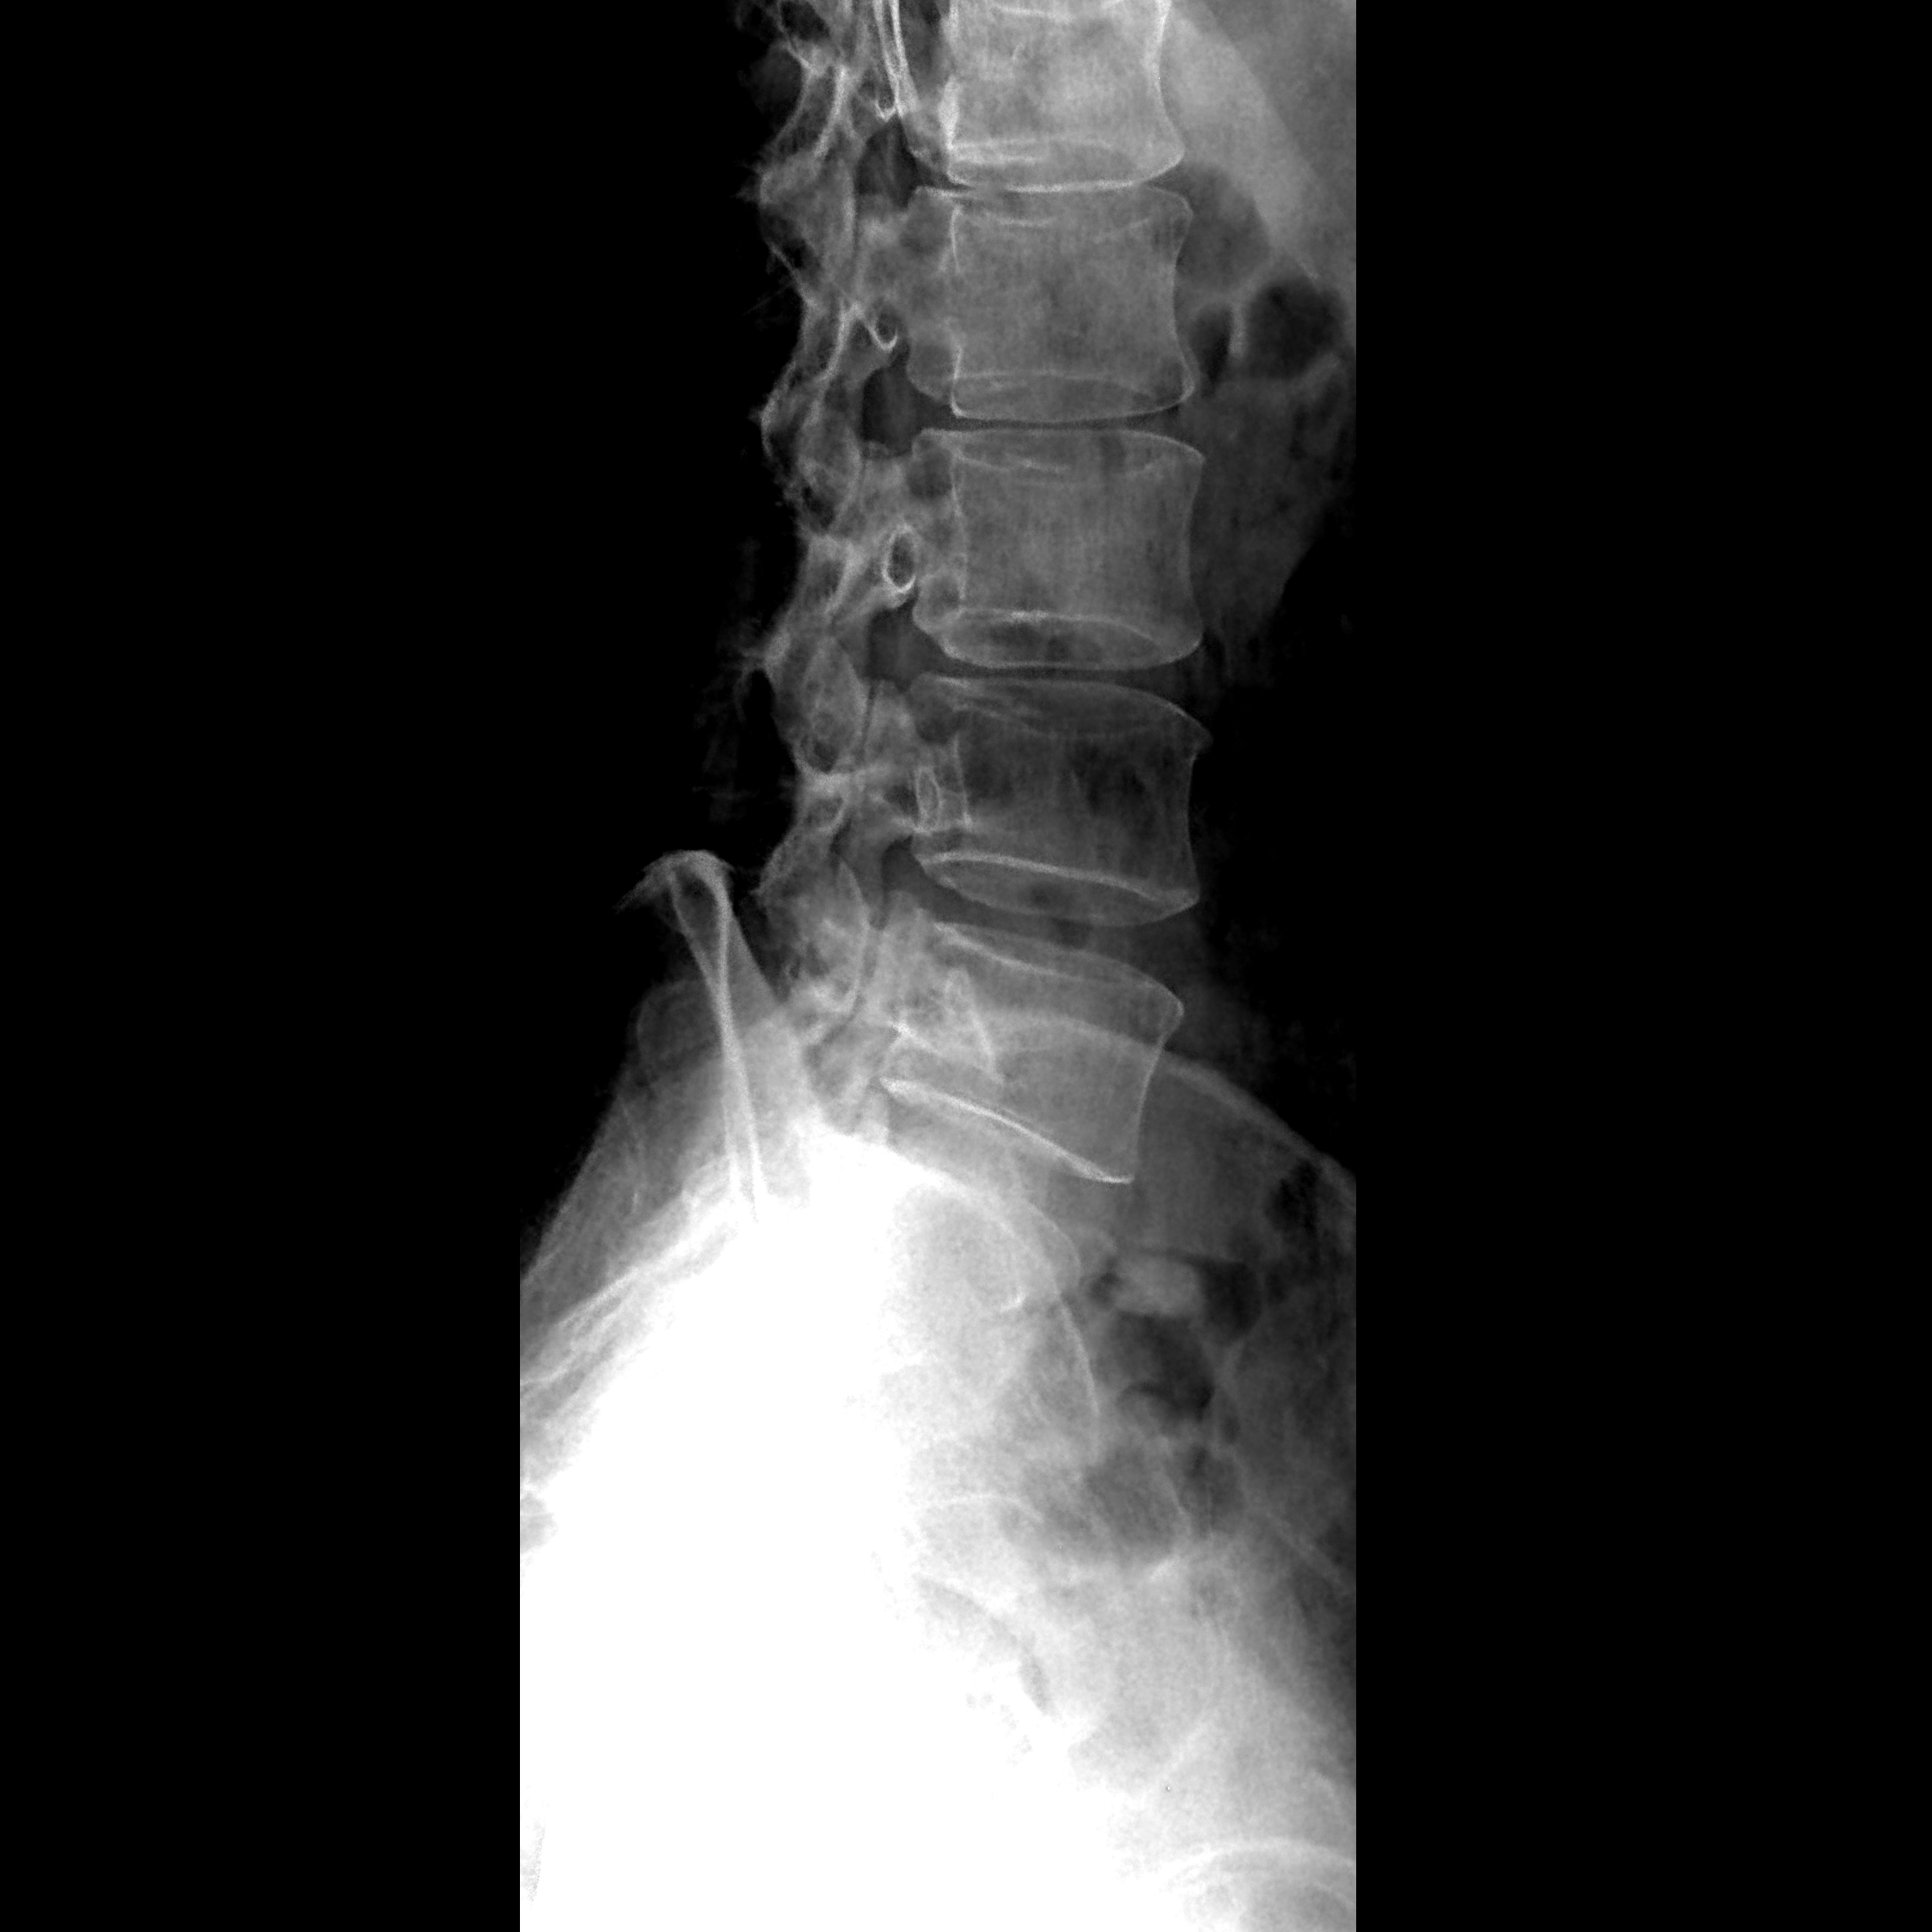

散射线伪影:X 线在穿透人体时,会产生散射线。如果没有有效的散射防护措施,散射线会到达探测器,使图像的对比度和清晰度下降,出现雾状或模糊的伪影,尤其是在拍摄较厚的部位,如腹部、骨盆等时,散射线伪影更为明显。

曝光参数不当伪影:曝光量过高或过低都会影响图像质量,产生伪影。曝光量过高时,图像会过度黑化,细节丢失,可能出现饱和伪影;曝光量过低时,图像噪声增加,显得模糊不清。

金属伪影:患者体内或体表的金属物品,如假牙、节育环、金属植入物、拉链、钥匙等,会对 X 线产生强烈的吸收和散射,在图像上形成高密度的阴影或放射状的伪影,严重干扰对周围组织的观察。